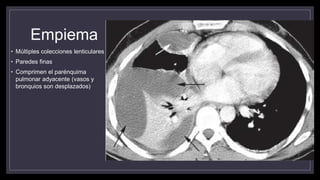

• Múltiples colecciones lenticulares

• Paredes finas

• Comprimen el parénquima

pulmonar adyacente (vasos y

bronquios son desplazados)